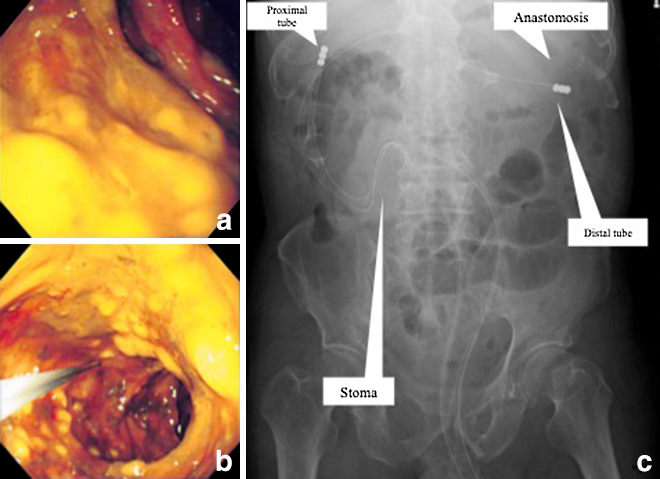

手術所見:右経腹直筋切開で開腹した.淡黄赤色の腹水を中等量認めた.可視範囲で盲腸~上行結腸の漿膜面に虚血性変化は認めなかった.双孔式回腸人工肛門を作成し,人工肛門より術中CFSを行った.右側結腸にも術前CFSで直腸からS状結腸に認めたものと同様のびまん性の偽膜の付着を認めた.粘膜に虚血性変化は認めなかった(Fig. 6a, b).人工肛門の肛門側から2本のイレウス管を挿入,1本は結腸結腸吻合部口側(distal tube)に,もう1本は上行結腸内(proximal tube)に留置し(Fig. 6c),それぞれのイレウス管よりNiflec® 1,000 mlで腸管洗浄を行い終刀した.

(a) (b) Intraoperative colonoscope through the stoma shows widespread pseudomembrane in the right-sided colon. (c) Two ileus tubes are placed through the anal limb of the stoma. The distal tube is placed at the oral side of anastomosis, and the proximal tube is in the ascending colon.